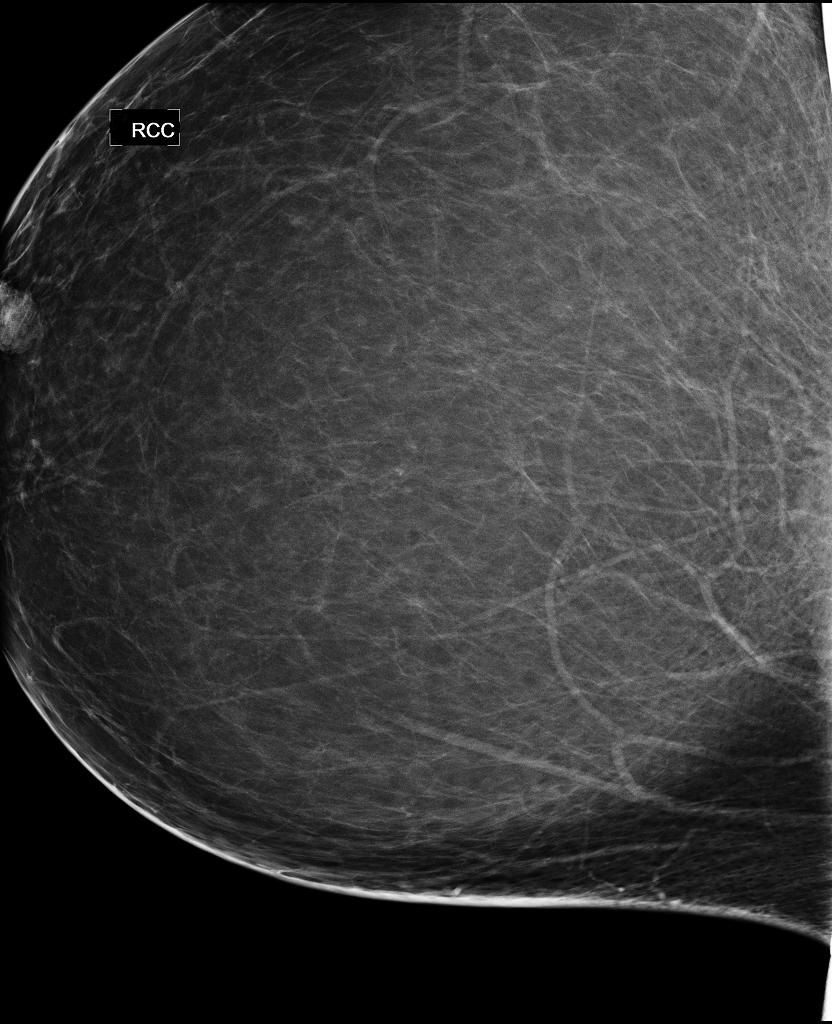

Direct radiography photon-counting systems detect more smaller breast cancers and DCIS, but also cause more recalls.

Digital mammography with a photon-counting system had higher cancer detection rates than traditional systems.

Tomosynthesis plus mammography images take 47 percent longer for radiologists to interpret than digital mammography alone.